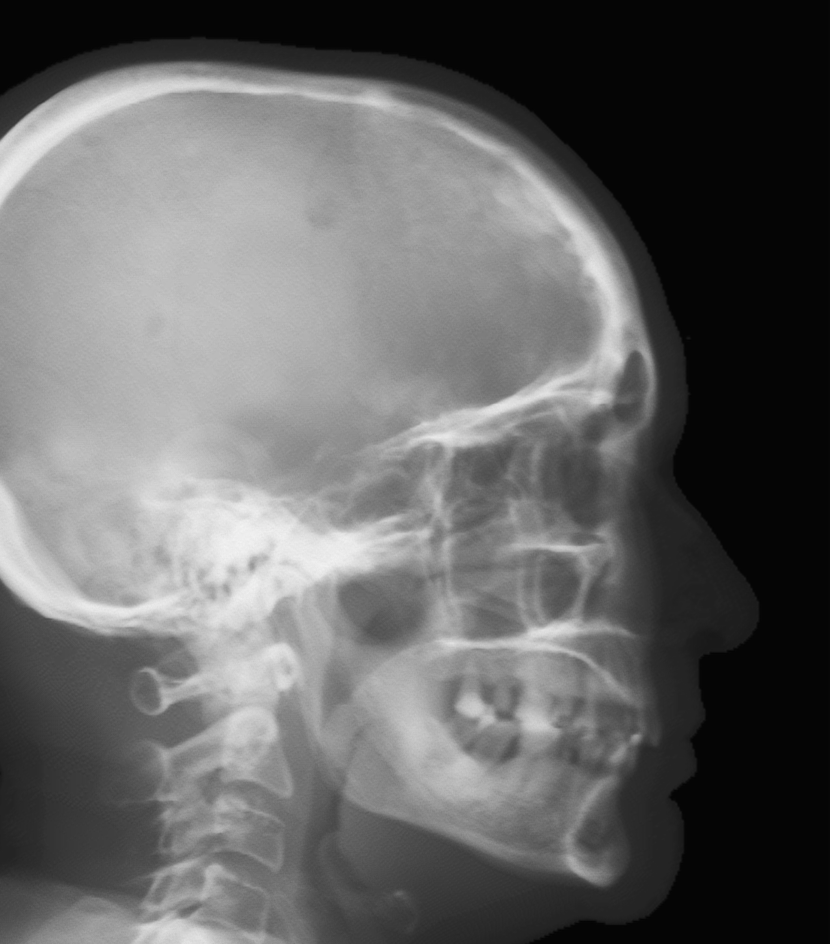

Refer to caption

(a) Real cephalogram

(b) Synthetic cephalogram

(c) Plot of samples and sigmoid curves

Fig. 2: Image contrast difference between real conventional cephalograms and RayCast synthetic cephalograms: (a) a real cephalogram example; (b) a RayCast synthetic cephalogram example; (c) the plot of samples between RayCast synthetic cephalograms and real cephalograms with an original sigmoid curve (red) and our proposed modified sigmoid curve (blue).

In Fig. 2, one real conventional cephalogram example and one example of 𝒈𝒈\boldsymbol{g} are displayed, where evident image contrast difference between these two images is observed. It is because the X-ray films used in conventional cephalograms have the special nonlinear optical property that the characteristic curve between optical density and logarithmized X-ray exposure has a sigmoid-like shape [42]. According to the Lambert-Beer law, the logarithmized X-ray exposure is equivalent to the attenuation integral. It indicates that the intensity relation between the desired cephalogram and the attenuation integral image 𝒈𝒈\boldsymbol{g} should also exhibit a sigmoid-like curve. Therefore, to make the image contrast of synthetic cephalograms similar to conventional cephalograms, a sigmoid intensity transform is necessary.